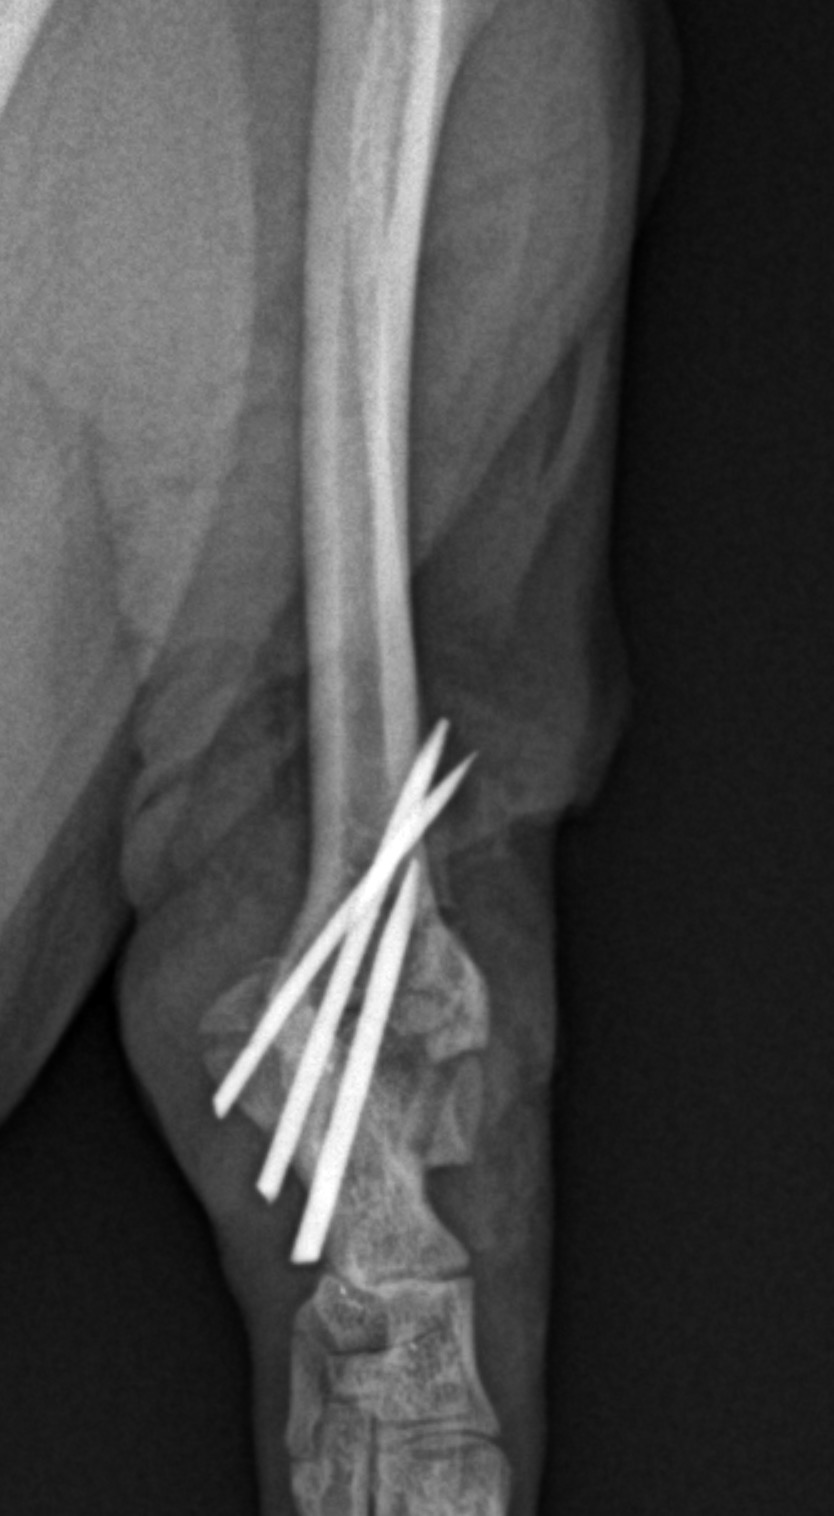

アキレス腱断裂 主治医よりアキレス腱断裂した患者さんが脚を着けなくなったので、なんとかして欲しいと連絡がありました。経関節ピンによる一時的な足根関節の仮固定とアキレス腱の縫合術により対応しました。しばらくは安静が必要です。 症例カテゴリー 放射線治療整形外科軟部組織外科脳神経外科内科腫瘍外科救急・集中治療リハビリテーション科腫瘍内科内視鏡科脳神経科呼吸器外科中医・漢方猫の腎移植循環器科